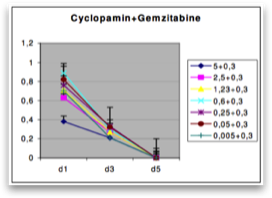

On the basis of the results of our mRNA expression analy- sis indicating Hedgehog pathway activation in pancreatic cancer, we inhibited the Hedgehog pathway with cyclopamine. To investigate whether the growth-inhibitory effect of cyclo- pamine may be related to inhibition of the Hedgehog signaling pathway, we used a GLI1 luciferase reporter assay. Transfection of the cells with a GLI1 luciferase reporter or with a nonfunctional GLI1 promoter variant indicated significant basal hedgehog ac- tivity in Capan-1 (Fig. 6A). Next, the pancreatic adenocarcinoma cells were treated with increasing amounts of cyclopamine. As shown in Figure 6B, in particular, Capan-1 showed a strong reduced viability for 3 days compared with the cells treated with PBS.

To determine whether growth inhibition by cyclopa- mine functions via blockade of Smo, we analyzed the PTCH1 expression in Capan-1 xenografts treated with cyclopamine. The application of cyclopamine led to a significant mRNA down- regulation of PTCH1 in the tumor tissue, indicating that cyclo- pamine treatment triggers a Hedgehog-related response in vivo. Moreover, a combined treatment with cyclopamine and the known antimetabolic agent gemcitabine resulted in a synergistic reduction of average tumor size compared with treatment of cy- clopamine or gemcitabine alone. Interestingly, previous studies indicated that growth inhibition of pancreatic cancer xenografts might be more pronounced when Hedgehog blockade was initiated concomitantly with the injection of tumor cells into nude mice. In our study, we could not confirm these findings.

In the present study, we show that the Hedgehog inhib- itor cyclopamine blocks Hedgehog signaling in pancreatic cancer cells in vitro and in vivo. However, it has been noted by different reports that different small-molecule inhibitors exhibit a much higher affinity for Smo than cyclopamine, they block the Shh func- tion at lower concentrations, they are water-soluble, and they have less toxic effects. Of note, small-molecule Hedgehog antagonists like IPI-269609 and GDC-0449 showed promising inhibitory effects in patients with pancreatic adenocarcinomas and other cancers like basal cell carcinomas.